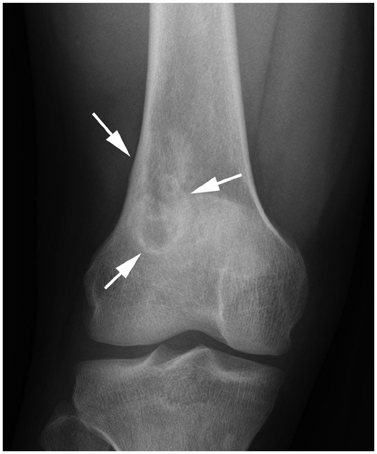

Systematic Approach of Sclerotic Bone Lesions Basis on Imaging Findings

- Sclerotic bone lesions are common, but there are diverse groups of tumors and non-tumorous lesions. Although plain radiograph and computed tomography can reveal important characteristics of these lesions, diagnosis is often challenging for radiologists. A systematic approach and familiarity with the imaging features of various sclerotic bone lesions may be greatly helpful for eliminating in the differential diagnosis. This review describes the systematic approach to diagnosing sclerotic bone lesions based on imaging findings.